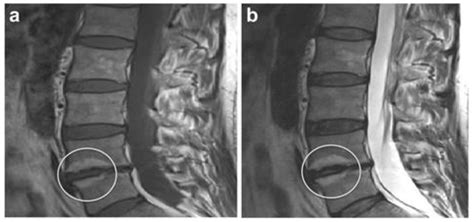

The Vacuum Disc Phenomenon describes the presence of gas, primarily nitrogen, within the intervertebral discs of the spine. When you look at an imaging study, this appears as a dark, linear, or localized radiolucency within the disc space. Essentially, it is a sign that the disc is undergoing degeneration or drying out.

The intervertebral discs act as shock absorbers between your vertebrae. Healthy discs are hydrated and flexible. As we age, these discs lose their water content, become thinner, and shrink. When a disc loses enough volume, a negative pressure, or "vacuum," is created within the disc space. This pressure drop causes nitrogen gas—which is normally dissolved in our body fluids—to pull out of the surrounding tissues and collect in the disc, forming what we see on the imaging as the Vacuum Disc Phenomenon.

• Spinal Instability: If the vacuum phenomenon is highly mobile (meaning the gas appears or disappears depending on whether you are standing or lying down), it may indicate that the spinal segment is unstable.